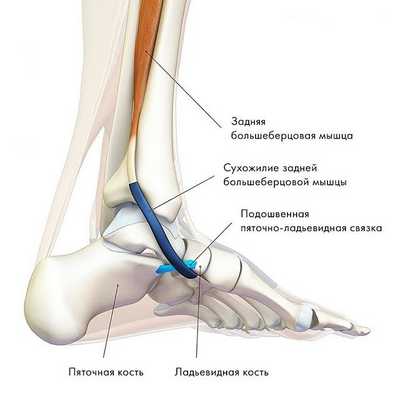

2. Брюшко задней большеберцовой мышцы начинается на задней поверхности большеберцовой и малоберцовой костей, а ее сухожилие идет вдоль задней поверхности внутренней лодыжки и на стопе прикрепляется к ладьевидной кости. Эта мышца осуществляет инверсию (внутреннюю ротацию) стопы и ее подошвенное сгибание в голеностопном суставе, однако основной ее функцией является поддержание продольного свода стопы. Сокращаясь, задняя большеберцовая мышца блокирует суставы среднего отдела стопы при ходьбе, и стопа тогда работает как жесткий рычаг. Разрыв сухожилия этой мышцы или даже его перерастяжение приводит к развитию плоскостопия.

Рис. Сухожилие задней большеберцовой мышцы.

Задняя большеберцовая мышца активна в течение фазы опоры, включается сразу после контакта пятки с опорой и быстро прекращает сокращаться после поднятия пятки. Ее брюшко начинается глубоко внутри задней части нижней конечности, сухожилие следует вниз до задней части медиальной лодыжки, где находится кпереди от сухожилия длинного сгибателя пальцев, заднего большеберцового нейрососудистого пучка (задняя б/б артерия, вена и нерв) и сухожилия сгибателя большого пальца. Все эти структуры ограничиваются удерживателем сгибателей возле медиальной лодыжки. Сухожилие задней б/б мышцы проходит в борозде позади и ниже медиальной лодыжки, разделяясь на 3 части у медиальной стороны тарана. Передняя часть прикрепляется к бугристости ладьевидной кости, средняя часть продолжается в плантарную тарзальную область и прикрепляется к плантарной части клиновидных костей, кубовидной и в основании 2, 3 и 4 метатарзальных костей. Задняя часть внедряется как пучок в переднюю часть нижней пяточно-ладьевидной связки. Медиальная лодыжка работает как многороликовый блок, позволяя сухожилию задней б/б мышцы изменять направление тяги, и эти точки прикрепления обеспечивают супинацию заднего и среднего отделов стопы во время переноса веса, в то время как происходит стабилизация арочной конструкции среднего отдела.